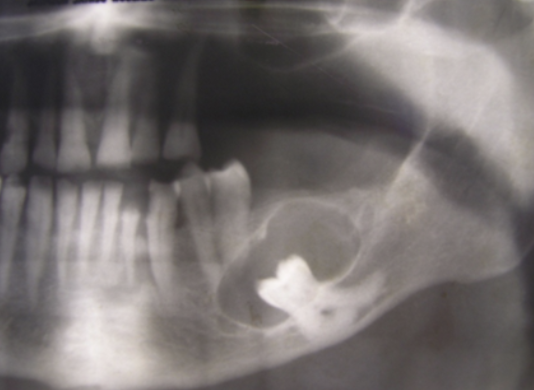

What pathology is imaged here?

Dentigerous cyst

Why are dentigerous cysts most commonly associated with lower 8s and upper 3s?

these teeth have highest rate of impaction

How do you interpret the difference between an enlarged follicle vs dentigerous cyst?

< 2.5mm = follicle

> 4.2mm = probable cyst

> 10mm = definite cyst

what is the aetiology of dentigerous cysts?

attachment of cyst lining at/near the ACJ suggests that these cysts occur as a result of cystic change in the remains of the enamel organ